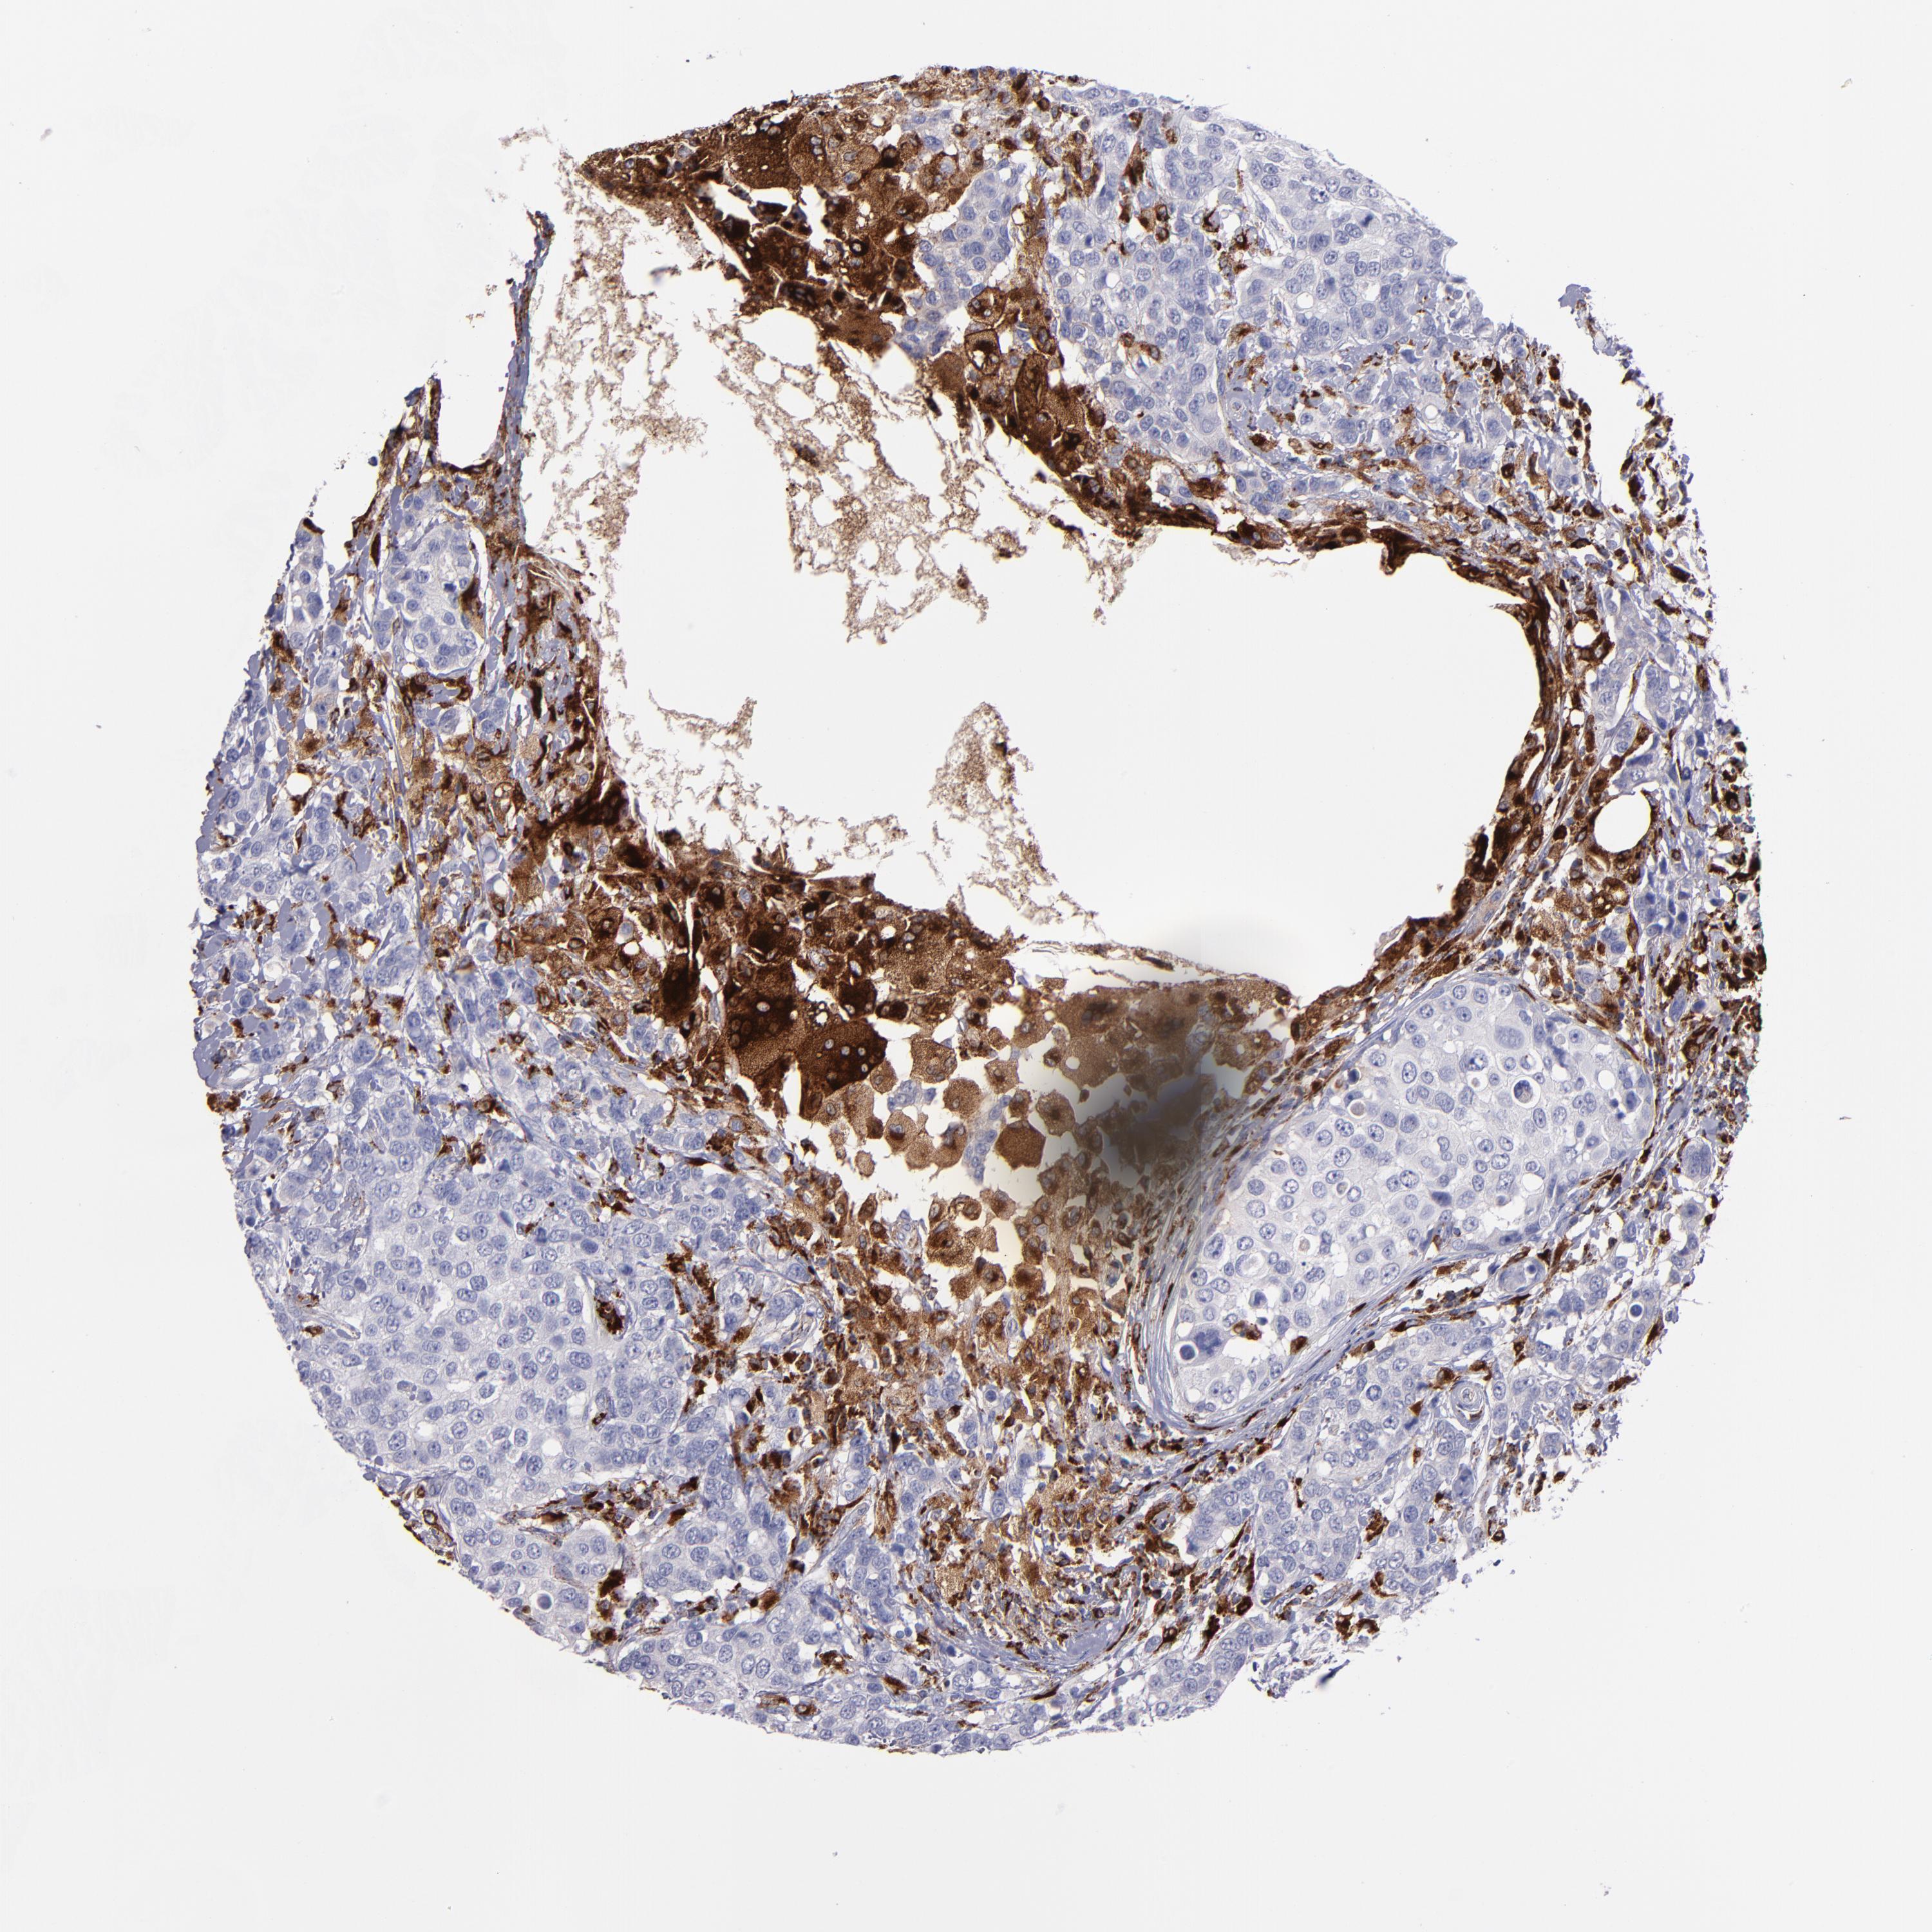

BRCA TCGA BRCA VALIDATION PROTEIN EXPRESSION

ANTIBODIES

AND

VALIDATION